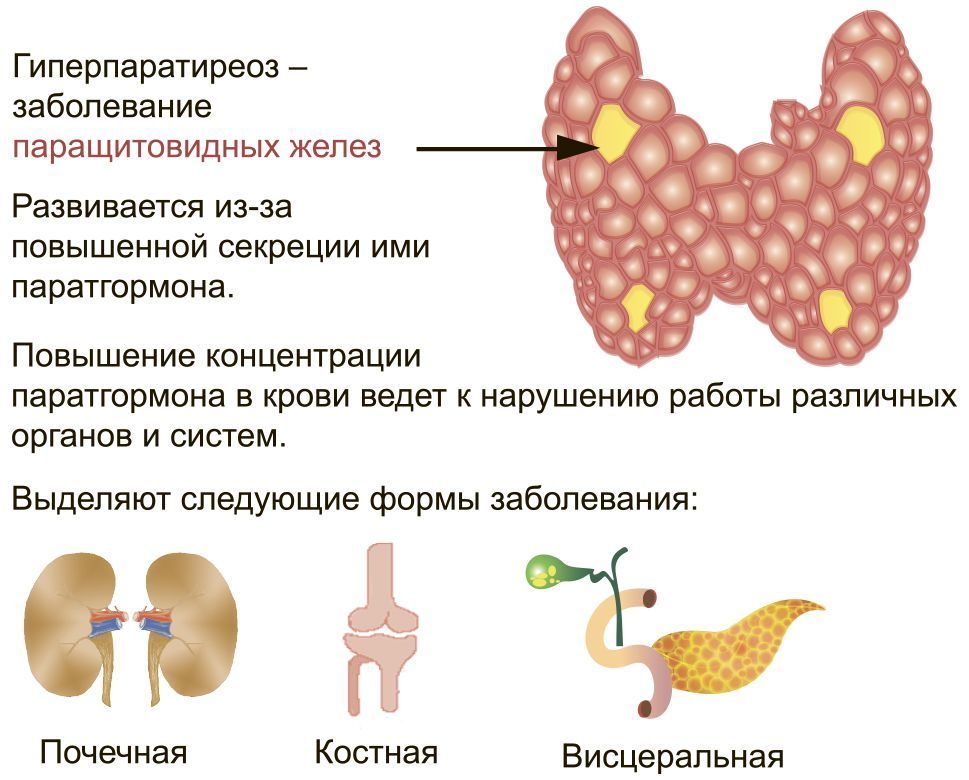

Иллюстрации и схемы по остеопорозу и паращитовидной железе